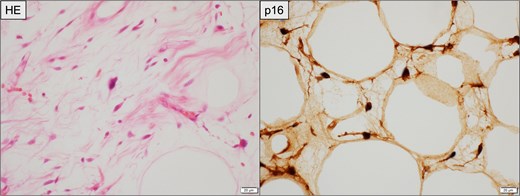

Histopathological findings of the resected recurrent tumor. Left (HE staining): Atypical spindle-shaped cells with hyperchromatic nuclei are observed within the fibrous stroma, consistent with WDLPS. Right (immunohistochemistry for p16): Tumor cells demonstrate diffuse nuclear and cytoplasmic positivity. Scale bar = 20 μm.